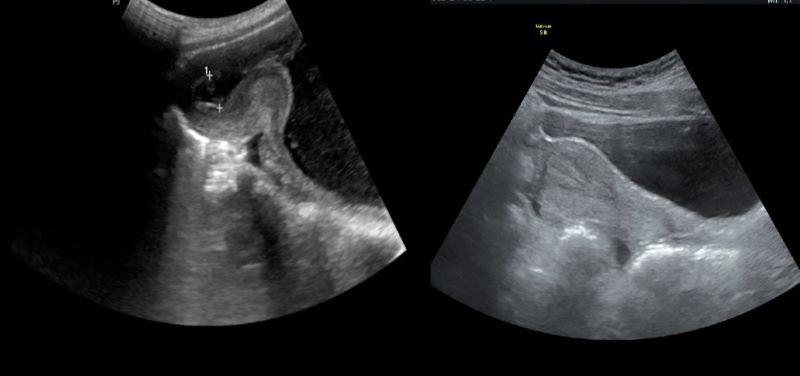

Suspecting that she had a disease, Ms. T also took the initiative to learn and found out that she had giant hypertrophy and bilateral breast sagging grade 4. Since 2015, she started reading about the disease, watching and researching good doctors and surgical centers, and beautiful cosmetic procedures. As she got older, Ms. T's breasts got bigger, so she was determined to have surgery.